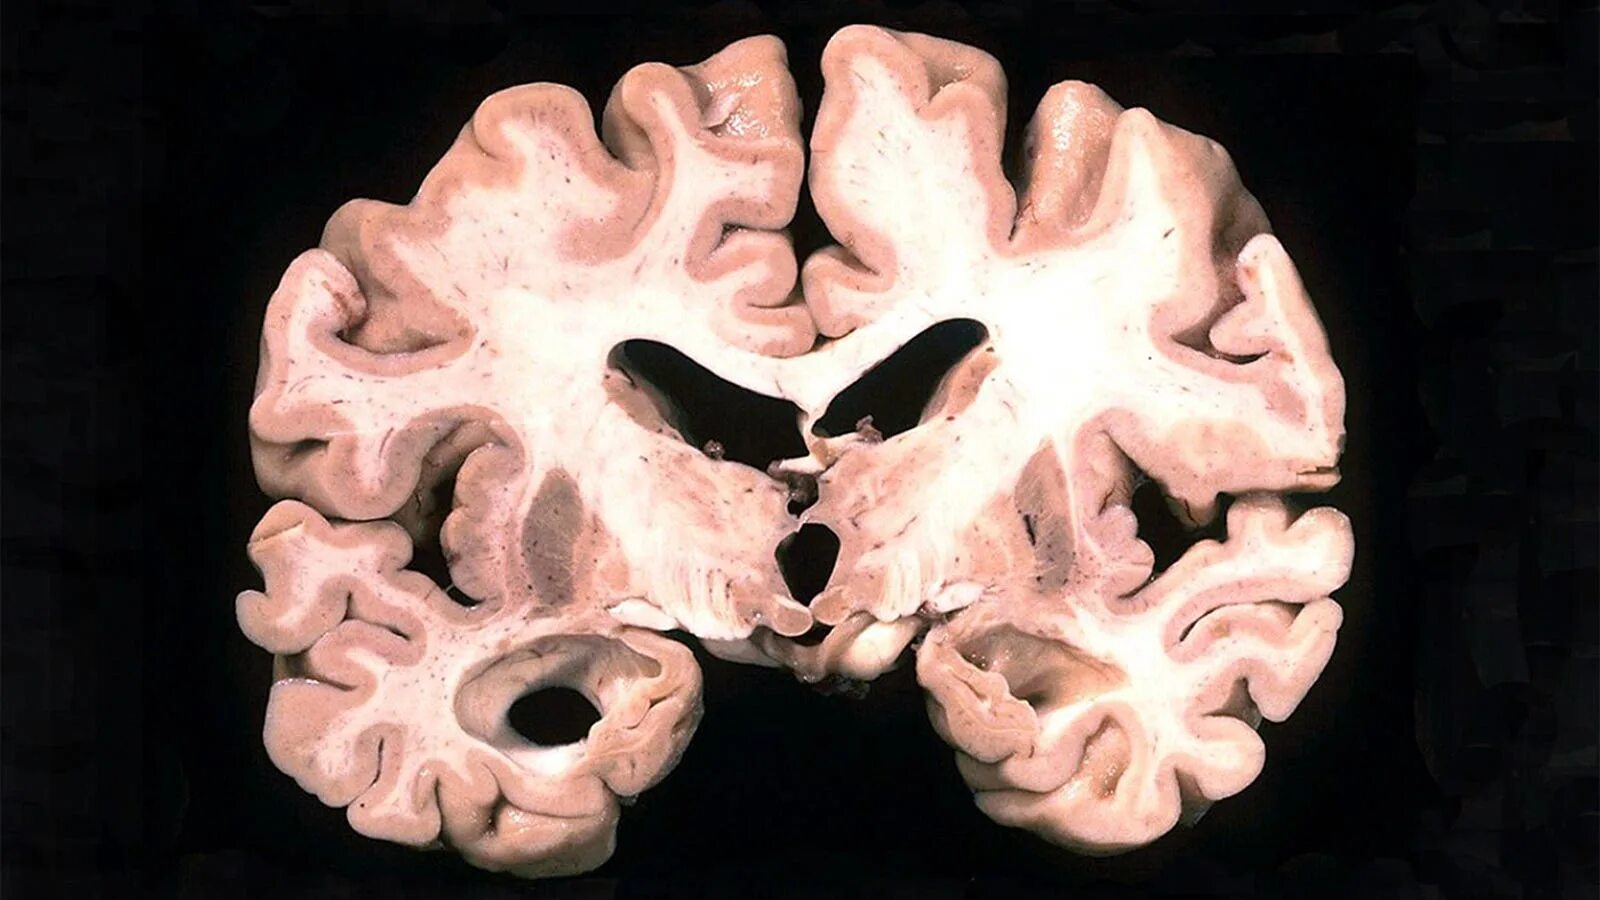

Болезнь головного мозга можно